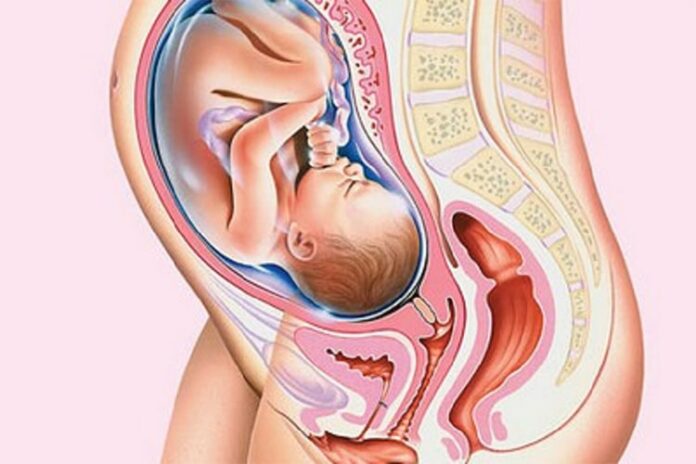

سرکلاژ دهانه رحم که بهعنوان بخیه دهانه رحم هم شناخته شده است نوعی روش جراحی برای بستن دهانه رحم هنگام بارداری میباشد. دهانه رحم بافتی است که هنگام زایمان برای خروج جنین از کانال زایمانی باز می شود تا جنین از رحم وارد واژن شود. در صورتی که پزشک فکر کند که جنین ممکن است خیلی زود به دنیا بیاید یا ممکن است به علت ضعف دهانه رحم مادر دچار سقط جنین شود این روش را پیشنهاد می دهد این کار فقط در بیمارستان یا یک مرکز جراحی انجام می شود و افراد بعد از انجام این عمل همان روز به خانه برمی گردند.

زمانی که بدن مادر برای زایمان آماده می شود دهانه رحم شروع به باز شدن میکند اما اگر دهانه رحم ضعیف باشد یا بنا به علل دیگری دچار مشکل باشد ممکن است دهانه رحم زودتر از زمان زایمان باز شود. در صورت بروز این اتفاق زایمان زودرس یا سقط اتفاق میافتد.